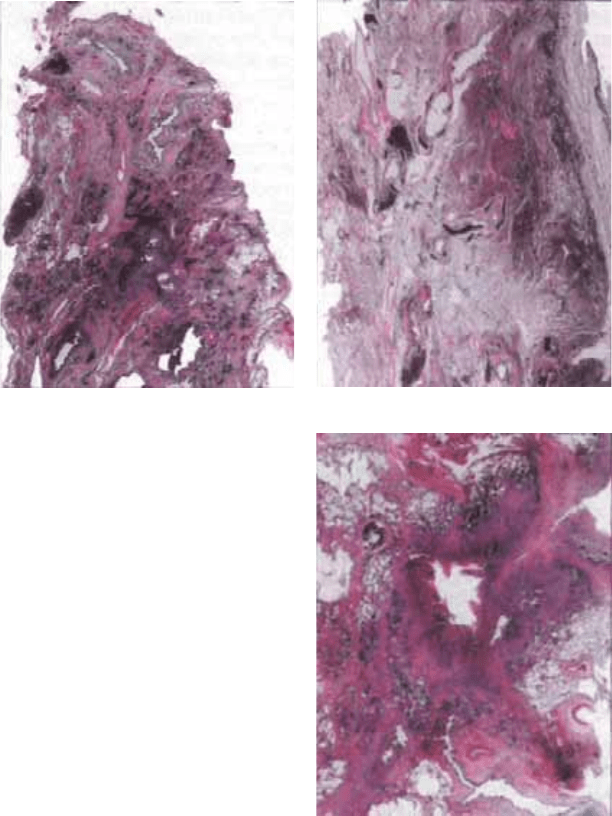

изменений. Среди фиброзной ткани определяются казеозные

очаги. Могут быть обнаружены и остаточные щелевидные ка-

верны с фиброзными стенками (рис. 15.2). Грубая деформа-